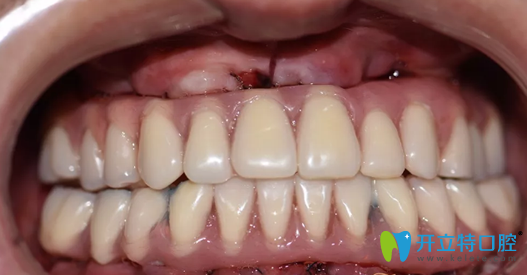

種植牙術(shù)后即刻照片及修復(fù)后CBCT影像:

重慶牙博士徐孟輝種植牙術(shù)后即刻照片及修復(fù)后CBCT影像

重新?lián)碛辛送暾例X的莫先生,是不是看上去年輕了很多,又恢復(fù)了他這個年齡應(yīng)該有的面貌。

種植完即刻牙齒情況照片:

徐孟輝種植完即刻牙齒情況照片

哇塞,這樣的牙齒是不是看上去順眼了很多,如果沒有人說的話,你能看出莫先生的牙是后天種植上去的嗎?